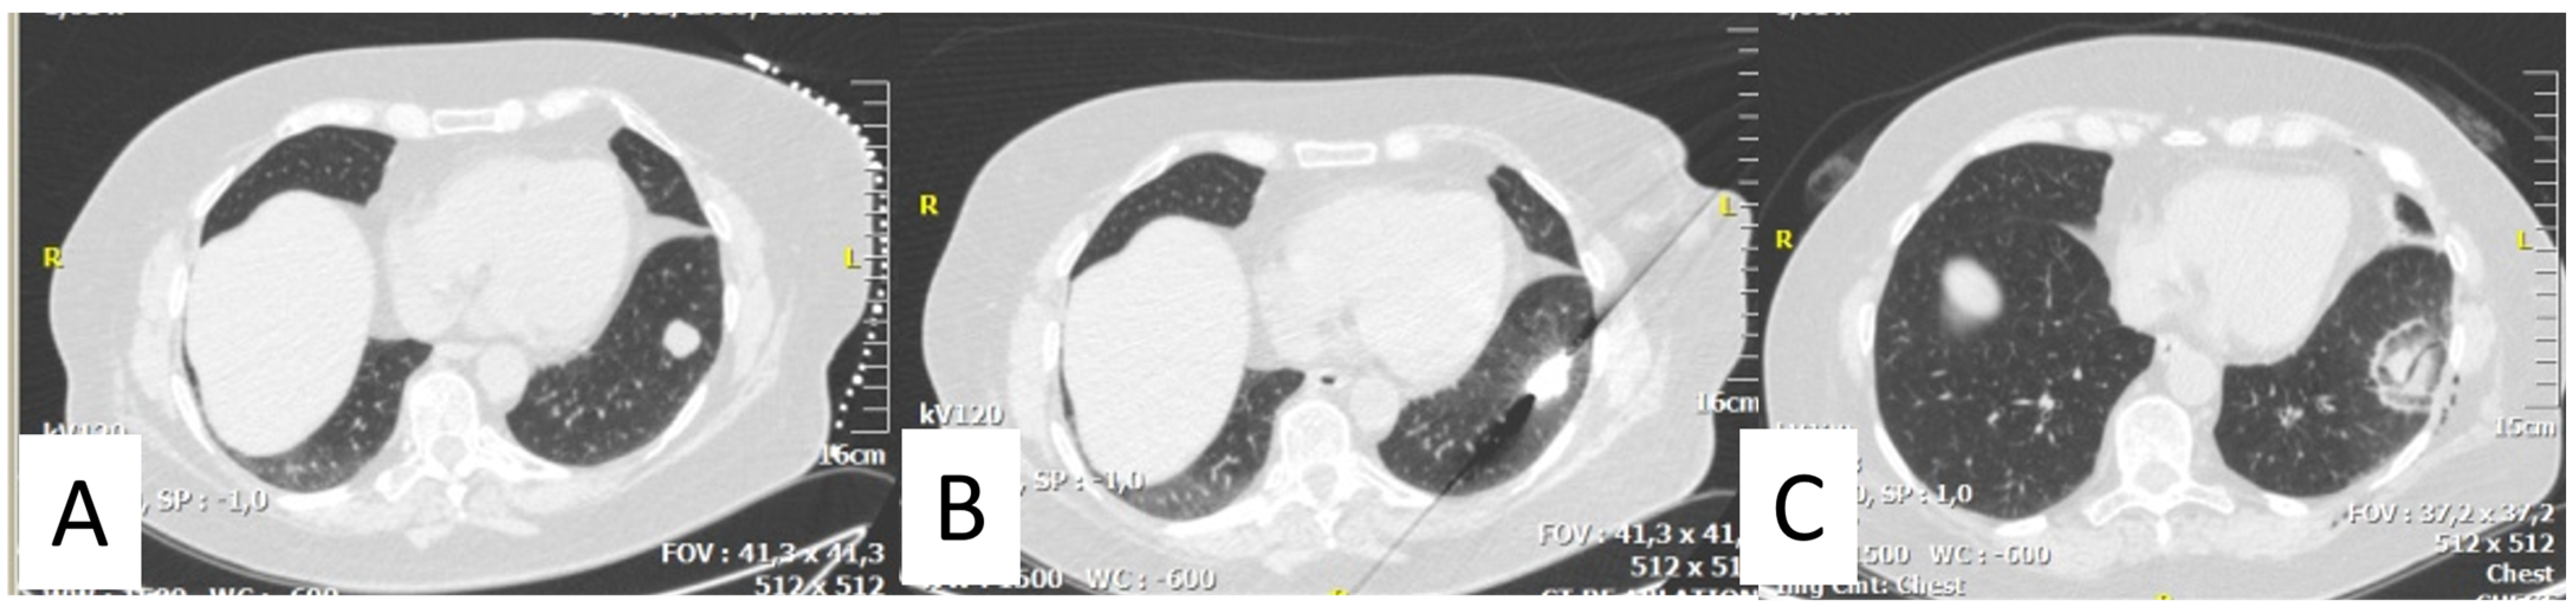

2. Thermal Ablation of Lung Metastasis

- Bourgouin, P.P.; Wrobel, M.M.; Mercaldo, N.D.; Murphy, M.C.; Leppelmann, K.S.; Levesque, V.M.; Muniappan, A.; Silverman, S.G.; Shepard, J.O.; Shyn, P.B.; et al. Comparison of percutaneous image-guided microwave ablation and cryoablation for sarcoma lung metastases: A 10-year experience. AJR Am. J. Roentgenol. 2022, 218, 494–504. [Google Scholar] [CrossRef] [PubMed]